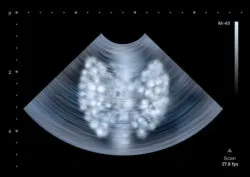

In particular, Onglyza thyroid cancer concerns remain at the top of the list.

Onglyza Thyroid Cancer Concerns

Onglyza is closely linked in its chemical composition to two other drugs also used to treat diabetes. These drugs, Victoza and Byetta, were found to have a link with the development of thyroid cancer. These drugs caused tumors in individuals, and some proved to be malignant.

Thyroid cancer, in general, is a very rare type of cancer, affecting approximately 600 patients per year.

A research study that included using Victoza caused rats to develop tumors in their thyroid gland. While this finding cannot necessarily be applied to humans, it does give additional information about the possibility of a link.